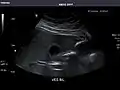

Aorta